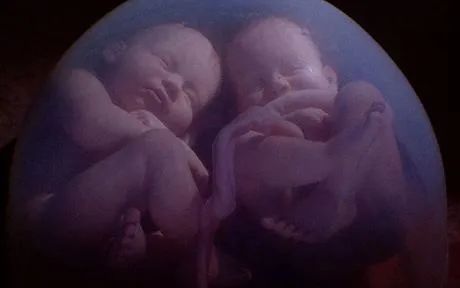

双胞胎的出现有两种可能,一种是由同一个受精卵(同卵双胞胎)分裂而成,另一种是由两个不同的卵子(异卵双胞胎)分别受精而成。

同卵双胎的形成则与上不同,是由同一个受精卵分裂而成的。这个受精卵一分为二(或更多),形成两个或多个胚胎。

由于他们出自同一个受精卵,接受完全一样的染色体和基因物质,因此他们的性别和相貌等等完全相同,且就像一个模子里出来的,有时甚至连自己的父母都难以分辨。这种相似不仅外形相似,而且血型、智力、甚至某些生理特征,对疾病的易感性等都很一致。我们常说的连体婴儿,实际上就是这种单卵双胎,只是由于当初受精卵分裂时的不完全造成了某些部位相连。